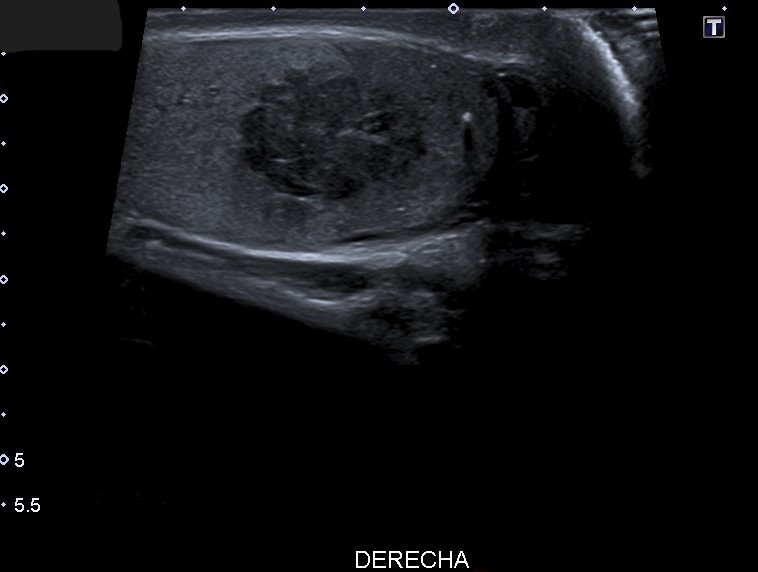

Ecografía escrotal: En testículo derecho se aprecia lesión heterogénea de predominio hipoecogénico con alguna calcificación grosera, polilobulada, de bordes mal definidos, con medidas aproximadas de 36 mm de diámetro máximo, con vascularización en su interior en el registro Doppler, sugestivo de proceso neoformativo testicular. No se objetiva engrosamiento epididimario ni de cubiertas escrotales.